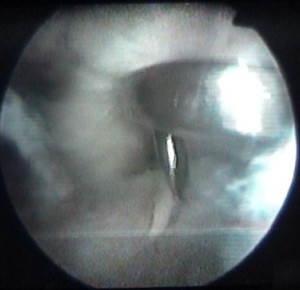

enlèvement d'un ménisque |